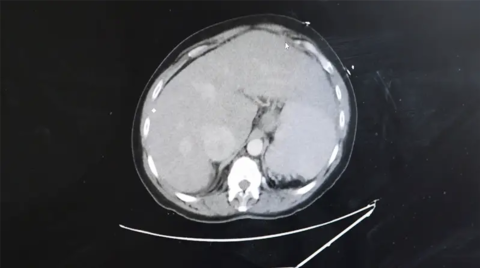

By 2023, Nadine had developed right heart failure, which caused congestion in her liver and led to liver cirrhosis. The natural progression of pulmonary arterial hypertension usually results in lung transplantation, according to Dr. Haythe, so she referred her to Dr. Arcasoy for lung transplant evaluation. The team listed her for transplant in January 2024.